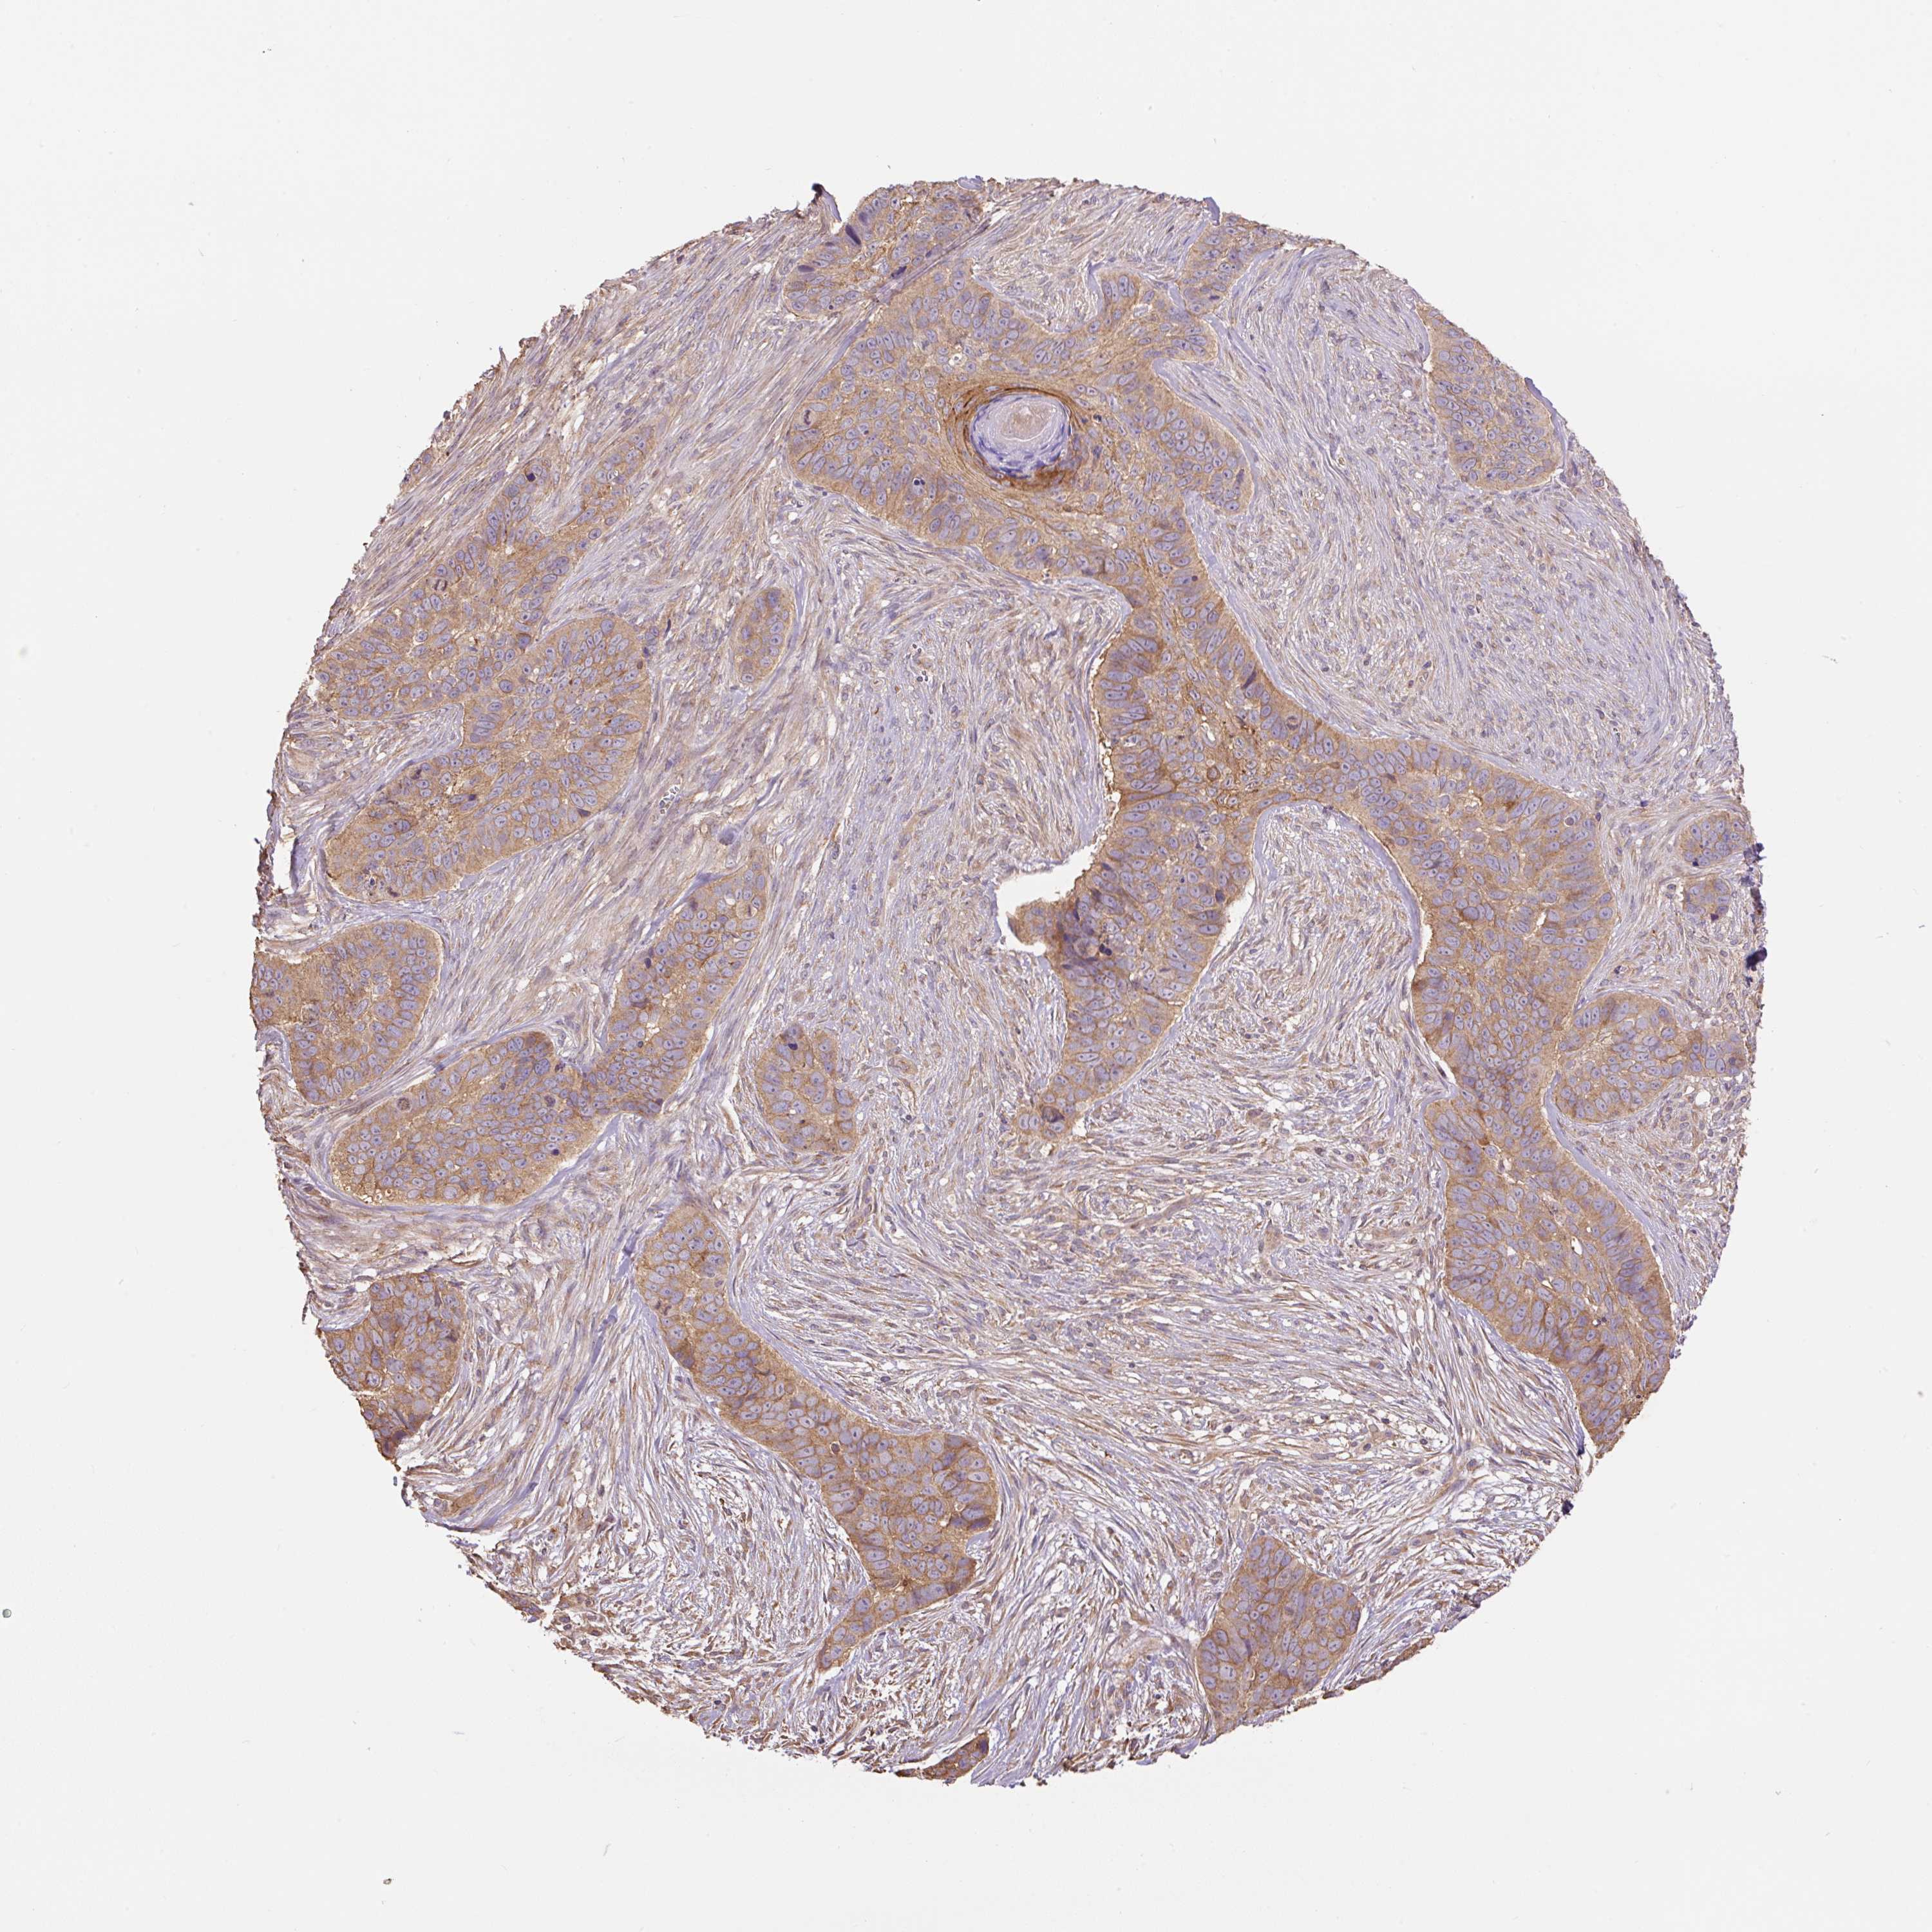

CANCER SKIN CANCER Show tissue menu

Basal cell and squamous cell cancer

SKIN CANCER - Protein expressioni

A mouse-over function shows sample information and annotation data. Click on an image to view it in a full screen mode. Samples can be filtered based on level of antibody staining by selecting one or several of the following categories: high, medium, low and not detected. The assay and annotation is described here.

Each image is clickable and will lead to virtual microscopy that enables deeper exploration of all samples and also displays staining intensity scores, fraction scores and subcellular localization as well as patient and tissue information for each sample.

Antibody HPA055942

Staining

High

Medium

Low

Not detected

Intensity

Strong

Moderate

Weak

Negative

Quantity

>75%

75%-25%

<25%

None

Location

Nuclear

Cytoplasmic/membranous

Cytoplasmic/membranous,nuclear

Basal cell carcinoma

Squamous cell carcinoma, NOS